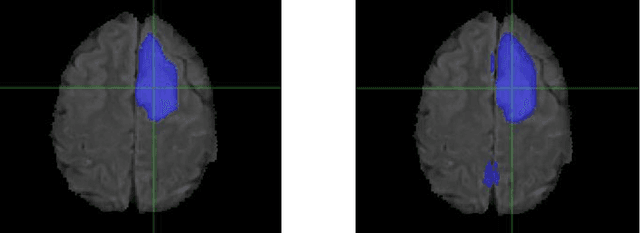

Abstract:Although machine learning (ML) has shown promise in numerous domains, there are concerns about generalizability to out-of-sample data. This is currently addressed by centrally sharing ample, and importantly diverse, data from multiple sites. However, such centralization is challenging to scale (or even not feasible) due to various limitations. Federated ML (FL) provides an alternative to train accurate and generalizable ML models, by only sharing numerical model updates. Here we present findings from the largest FL study to-date, involving data from 71 healthcare institutions across 6 continents, to generate an automatic tumor boundary detector for the rare disease of glioblastoma, utilizing the largest dataset of such patients ever used in the literature (25,256 MRI scans from 6,314 patients). We demonstrate a 33% improvement over a publicly trained model to delineate the surgically targetable tumor, and 23% improvement over the tumor's entire extent. We anticipate our study to: 1) enable more studies in healthcare informed by large and diverse data, ensuring meaningful results for rare diseases and underrepresented populations, 2) facilitate further quantitative analyses for glioblastoma via performance optimization of our consensus model for eventual public release, and 3) demonstrate the effectiveness of FL at such scale and task complexity as a paradigm shift for multi-site collaborations, alleviating the need for data sharing.

Abstract:Every year thousands of patients are diagnosed with a glioma, a type of malignant brain tumor. Physicians use MR images as a key tool in the diagnosis and treatment of these patients. Neural networks show great potential to aid physicians in the medical image analysis. This study investigates the use of varying amounts of synthetic brain T1-weighted (T1), post-contrast T1-weighted (T1Gd), T2-weighted (T2), and T2 Fluid Attenuated Inversion Recovery (FLAIR) MR images created by a generative adversarial network to overcome the lack of annotated medical image data in training separate 2D U-Nets to segment enhancing tumor, peritumoral edema, and necrosis (non-enhancing tumor core) regions on gliomas. These synthetic MR images were assessed quantitively (SSIM=0.79) and qualitatively by a physician who found that the synthetic images seem stronger for delineation of structural boundaries but struggle more when gradient is significant, (e.g. edema signal in T2 modalities). Multiple 2D U-Nets were trained with original BraTS data and differing subsets of a quarter, half, three-quarters, and all synthetic MR images. There was not an obvious correlation between the improvement of values of the metrics in separate validation dataset for each structure and amount of synthetic data added, there is a strong correlation between the amount of synthetic data added and the number of best overall validation metrics. In summary, this study showed ability to generate high quality synthetic Flair, T2, T1, and T1CE MR images using the GAN. Using the synthetic MR images showed encouraging results to improve the U-Net segmentation performance which has the potential to address the scarcity of readily available medical images.